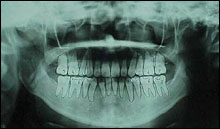

Panorama